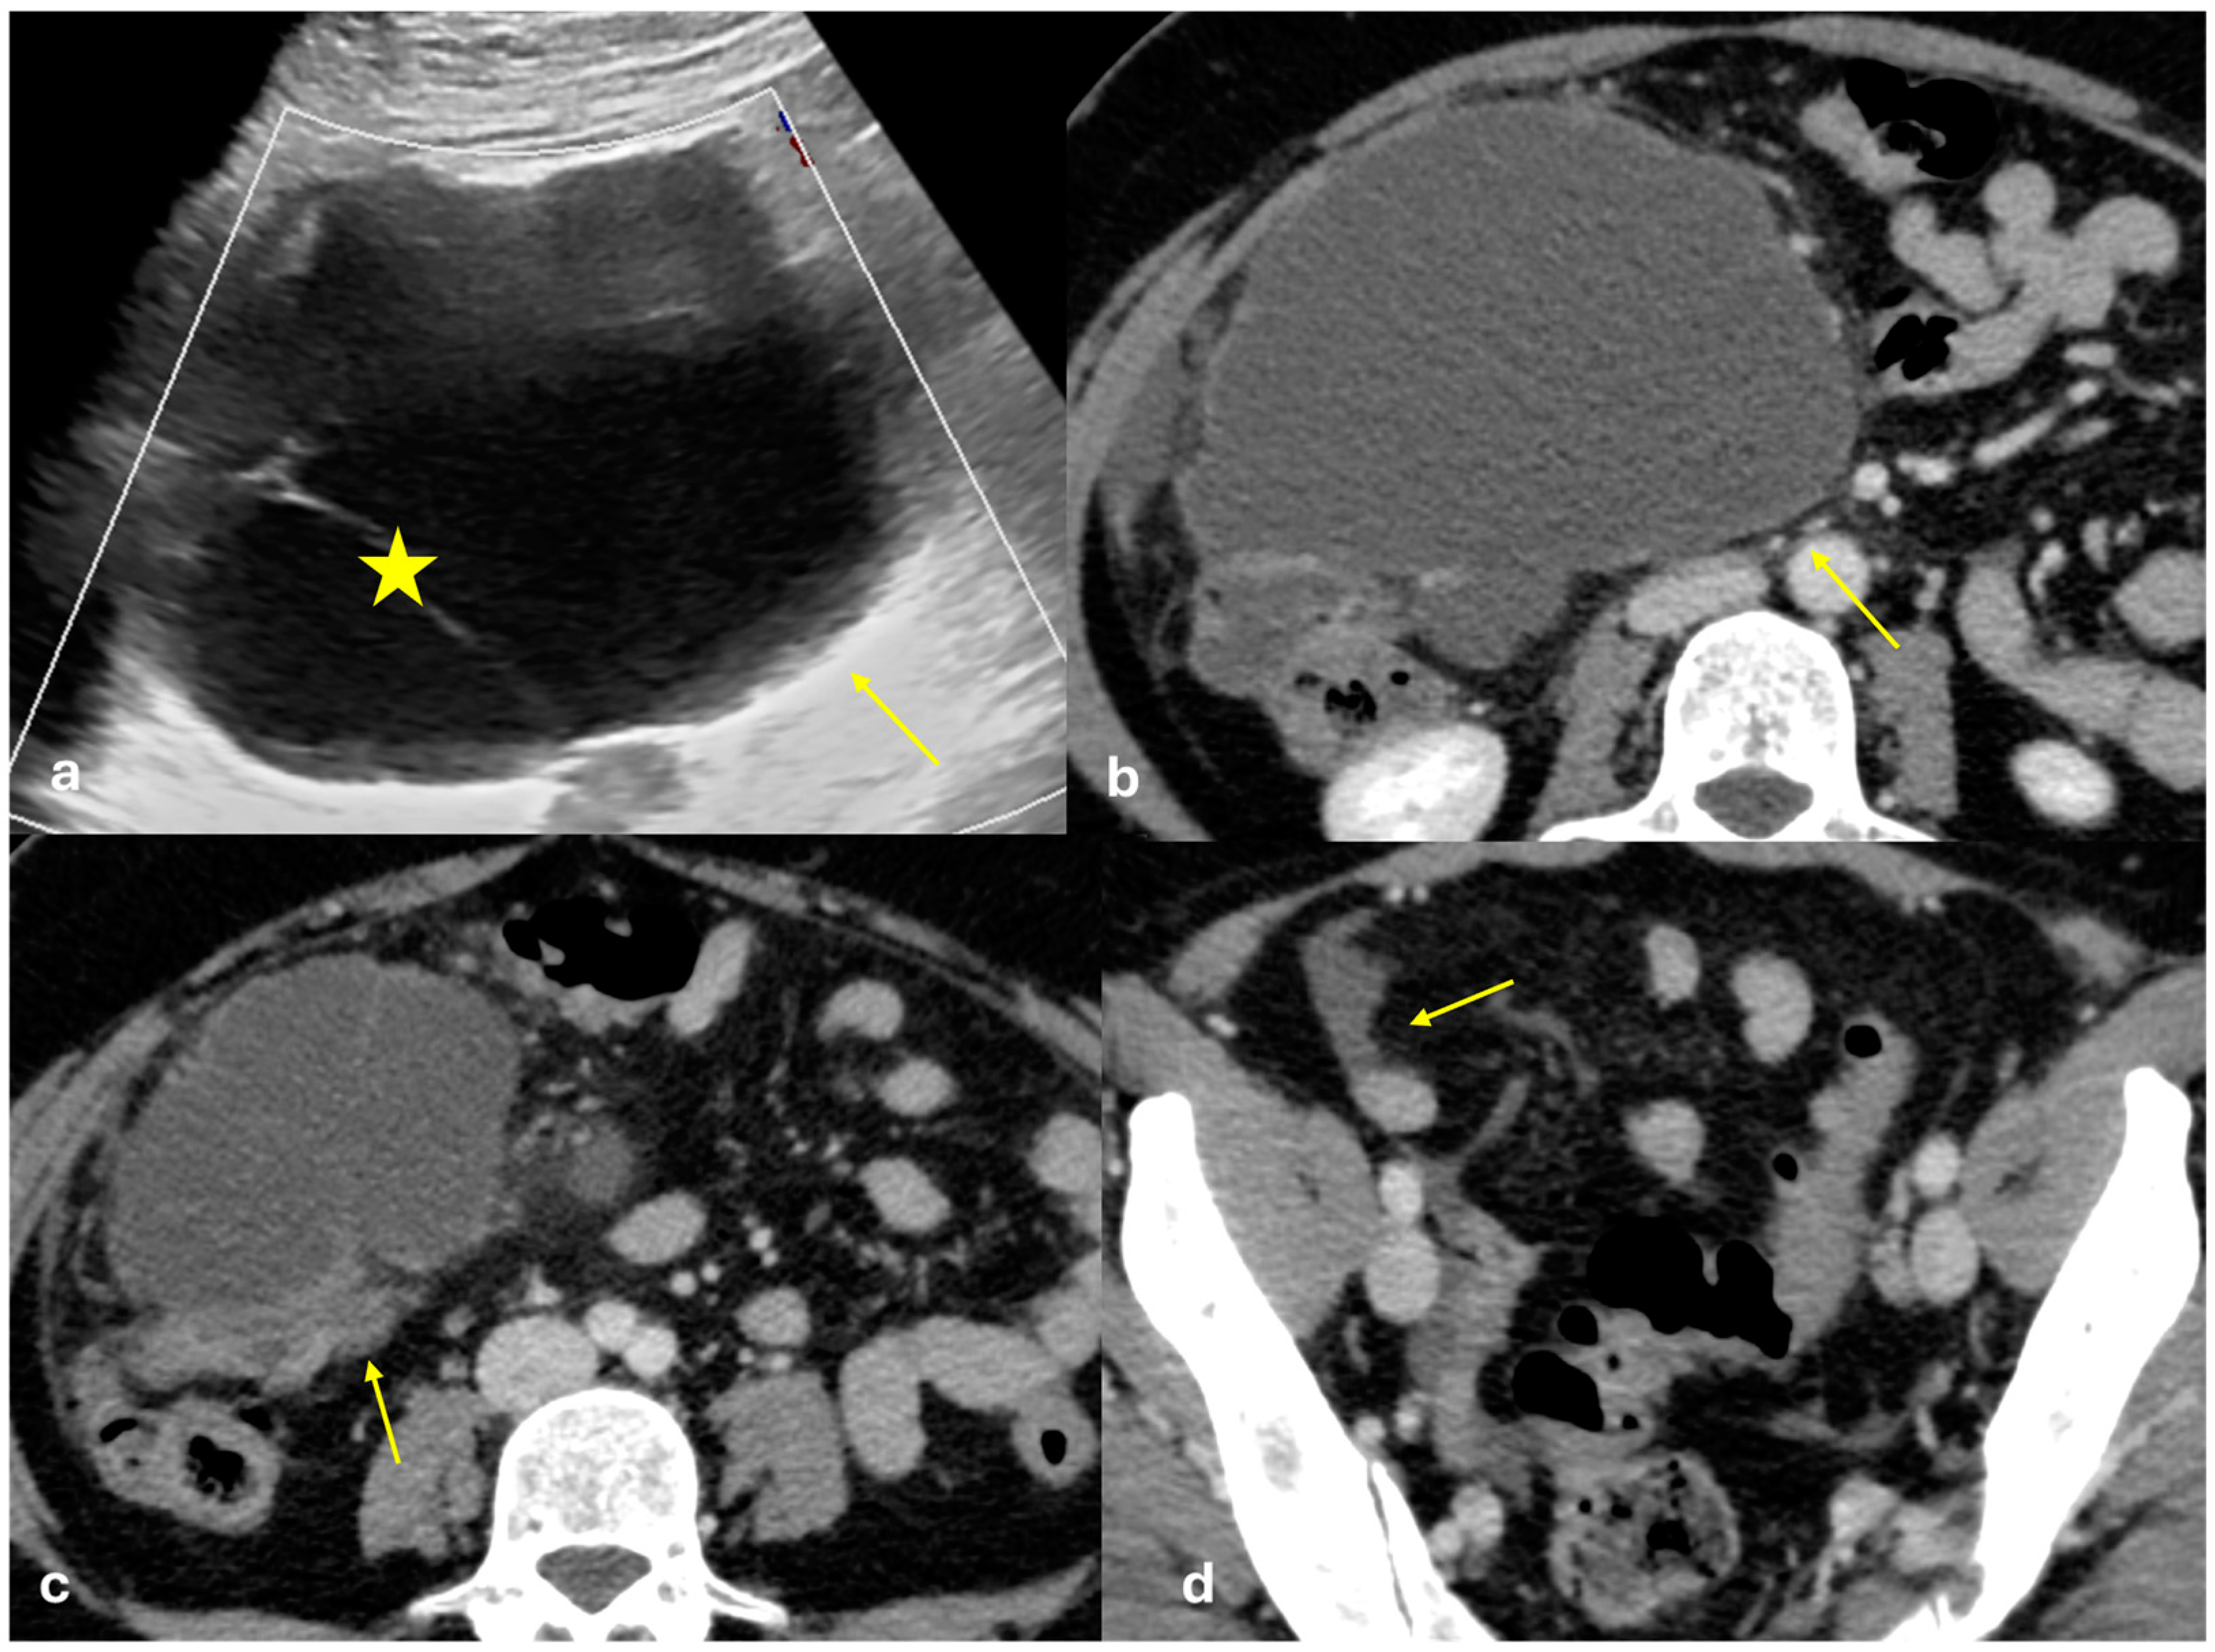

Mesenteric Pseudocyst